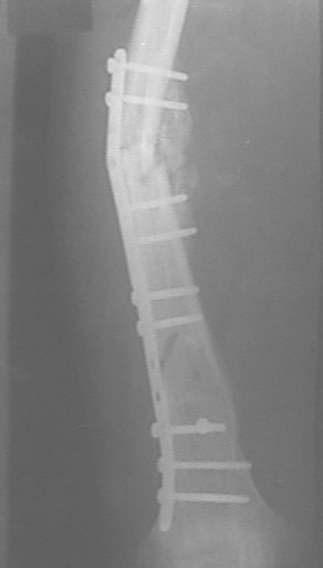

Неправильно сросшийся перелом голени

Уважаемые коллеги! На консультации больной предъявляет жалобы на хромоту (укорочение - 2см), боль в месте перелома при нагрузке (спортсмен).

Семь месяцев назад получил закрытый перелом, лечился консервативно в одной из больниц города. Как-бы кто лечил? Сам склоняюсь к LCP с костной пластикой.

Юрий Алексеевич, привет. А перелом то вроде сросся! -правда с варусом - угол можно посчитать у Вас по снимкам (в письме - суставов нет в прямой проекции). Я бы не спешил, с открытой хирургией тем более. Риски велики. Укорочение абсолютное тоже мизерно. А коррекцию оси сделал бы попозже малоинвазивным методом по Илизарову ГА.

Интересно, какие соображения легли в основу выбора? Вроде LCP и сильно недешевы, и демонстрируют свои замечательные свойства в большей мере при околосуставных проблемах?

У нас, наверно, была бы сделана чрескожная остеотомия малоберцовой кости, формирование и рассверливание канала большеберцовой, закрытая остеоклазия, и закрытое же штифтование. За счет устранения варуса дефицит длины уменьшится. Можно и подтянуть дистрактором одномоментно.

При невозможности или чрезмерной травматичности одномоментного восстановления длины можно пойти двухэтапно (аппарат, потом гвоздь). Похожий пример см. тут. Прошло уже года полтора после остеосинтеза. Может, коллега Зырянов покажет годичный результат, если есть?

Александр Николаевич, к сожалению больной не является на контрольные осмотры. Я последний раз видел больного, когда прошло 7 месяцев после операции БОС. У него все хорошо. Каких либо жалоб и ограничений в нагрузке нет. Высылаю снимки до операции и последние снимки.